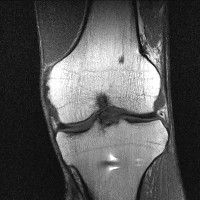

무릎 mri 간단히 봐주실 수 있으시나요 ㅠㅠ

안녕하세요 8년전 십자인대 수술하고 최근 무리한 운동에 무릎 불편감이 생겨서

mri 찍었습니다.

진단결과는 첫 찍은 병원에서 활액막염 이라는 진단을 받았습니다. 혹시 봐주실 수 있으실까요?

올라온 MRI가 단편적이라서 정확한 진단에 어려움이 있지만 십자인대에는 큰 이상이 있지는 않은것 같으며, 무릎관절내 물이 있는 것으로 보아 활액막염의 진단이 맞을 것 같습니다.

하지만 단편적인 영상이기 때문에 촬영병원에서 정확한 판독지 등을 받으시는 것이 좋겠습니다.